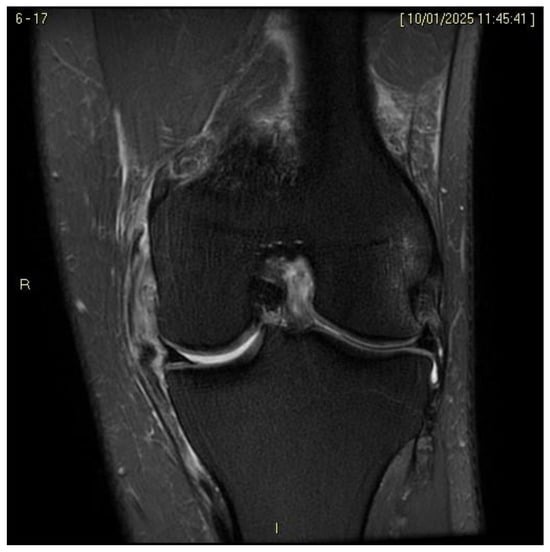

4.4. Magnetic Resonance Imaging (MRI) in the Diagnosis of ACL and MCL Injuries